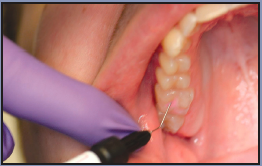

OptraGate

The OptraGate (Figure 4) offers facilitated access to the oral cavity due to gentle perioral retraction of the lips and cheek. It is an auxiliary aid that enables the treatment field to be enlarged easily, effectively and comfortably. OptraGate, available in two adult sizes - "regular" and "small" - is entirely latex-free and can therefore be used in patients with latex allergies.